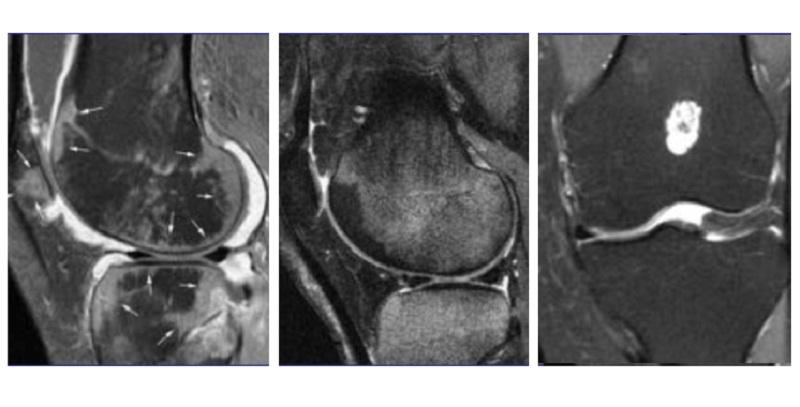

Люди, столкнувшиеся с трабекулярным отеком костного мозга, часто делятся своим опытом и рекомендациями. Многие отмечают, что важным шагом в лечении является правильная диагностика, которая позволяет определить причины отека. Врачи советуют проводить комплексное обследование, включая МРТ и анализы крови.

Изменения в костном мозге можно выявить с помощью магнитно-резонансной томографии и анализа крови.

Для точной диагностики рекомендуется провести МКТ костной ткани. Врачи настоятельно советуют применять медикаментозное лечение, что существенно снижает риск прогрессирования заболевания. Для замедления процессов разрушения кости назначаются препараты на основе хрящевой ткани.